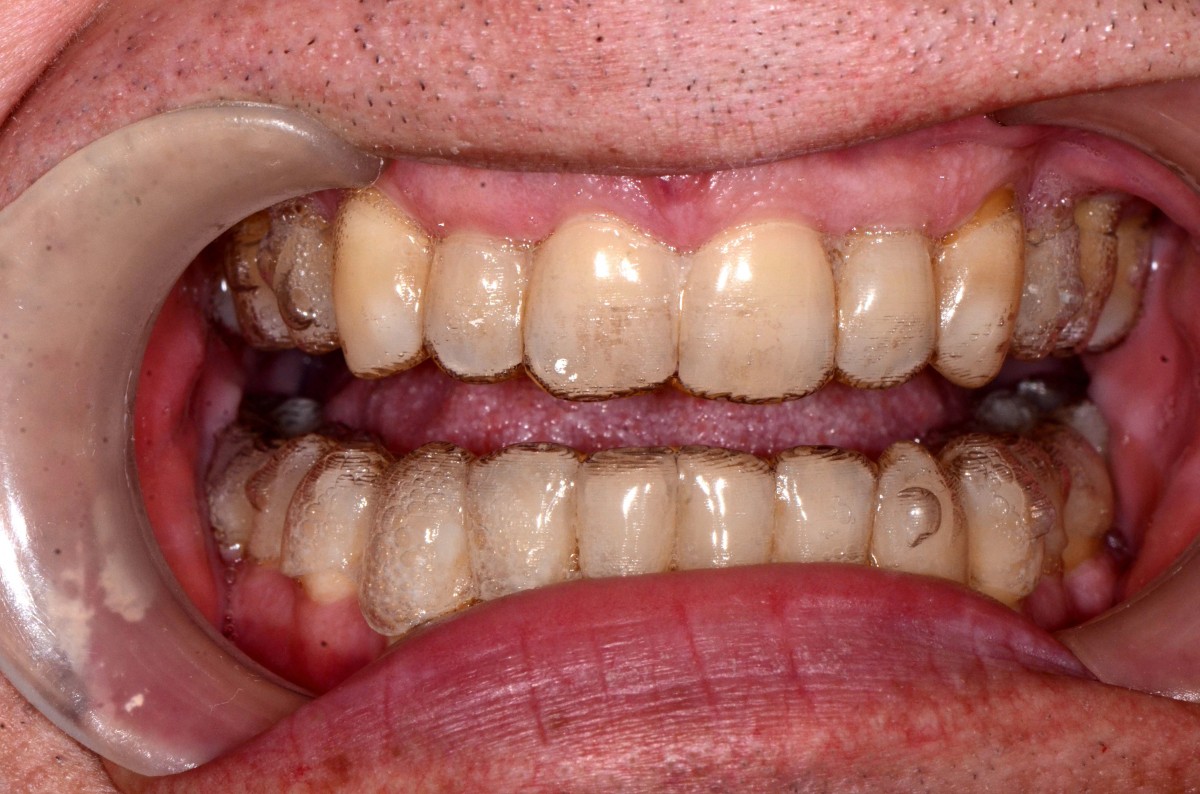

G.L., 51 years old patient, pre- sented to the clinic with Class I malocclusion, deep bite with complete coverage of lower in- cisors, big median diastema between teeth #11 and #21, lack of interdental papilla and poor oral hygiene (figs. 3, 4).

Lower incisors erupted verti- cally and created 2 planes of occlusion and exaggerated curve of spee in the lower arch. The upper lip “pushed” the an- terior incisors lingually and consequently the bite was deepened. Oral hygiene is poor mainly due to the crowding of the lower incisors. The upper diastema resulted in the loss of the interdental papilla between the central incisors (figs. 5, 6).

Patient had gone through pre- vious orthodontic treatment

with extraction of upper first premolars (#14, #24). Space between #11-#21 is slowly opened during the years and space start to develop distally to the upper lateral incisors. Lower incisors are hitting traumatically the palate creat- ing proliferation of the epithe- lium and constant inflamma- tion. Lower anterior crowding is around 4.5 mm (#33-#43) (figs. 7, 8).